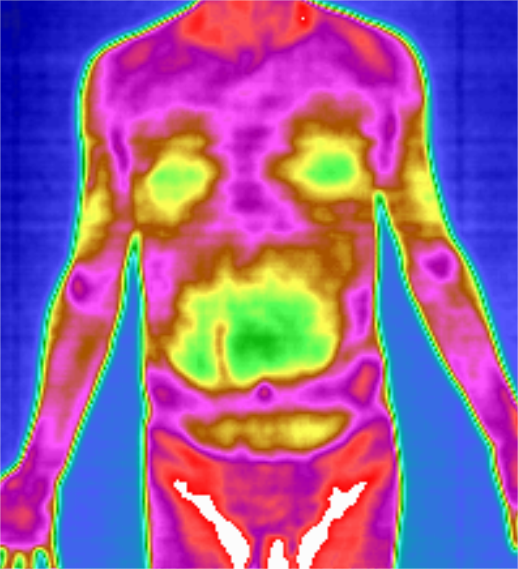

红外热成像 | 您的温度决定了您的健康

“赤橙黄绿青蓝紫,谁持彩练当空舞”当彩虹映入人体,穿透您的身体绘制出一幅彩色的蓝图就可以看出你的身体健康状况!你信吗?来让红外热成像仪告诉你什么是红外热成像仪?红外热成像仪是通过动态地、客观地监测人体温度分布,进行温差摄像的仪器。能早期反映细胞代谢(温度)异常,提早预